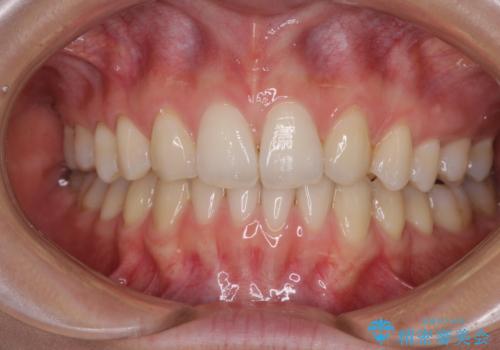

外に飛び出して磨きにくい奥歯と上下前歯の隙間 インビザラインによる矯正治療

- 上下前歯の隙間と、外側を向いていて歯磨きのしにくい奥歯を気にして来院された患者様です。

下顎前歯が1本欠損しており、上下アーチはアンバランスとなりますが、インビザラインを用いて上下の隙間を改善しながら歯列を整えることとしました。

下顎前歯の1本欠損により左右の咬合が不安定となり、治療経過で噛みにくい状態が続きましたが、最終的には違和感なく噛めるようになりました。